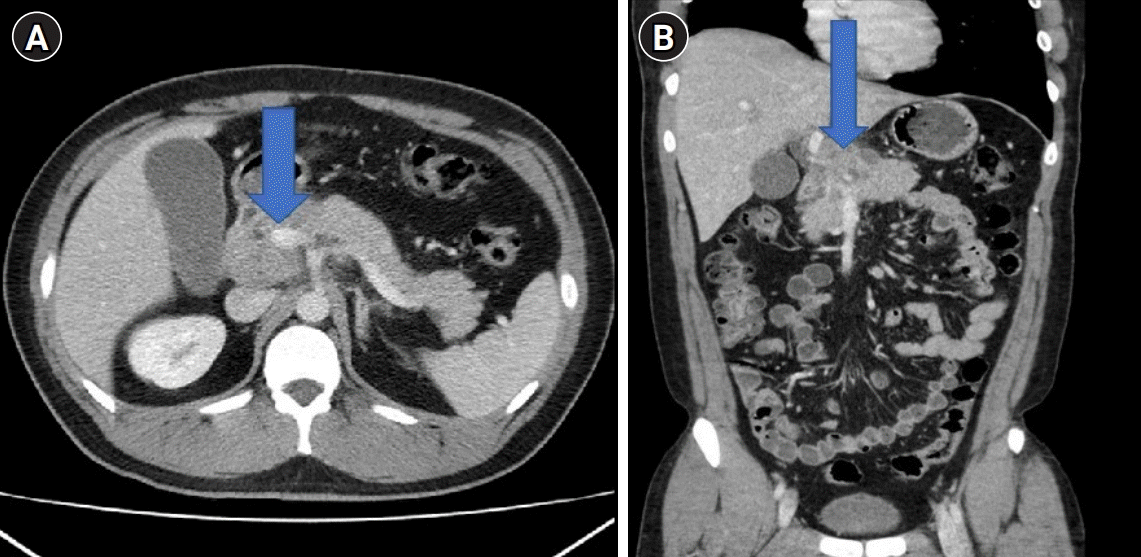

Chest radiography revealed the absence of active lesions. A chest CT revealed no active lesions. Abdominal CT revealed a large mass-like lesion in the pancreatic head and mild dilatation of the common bile duct (CBD). The distal CBD was encased in a mass-like lesion (Fig. 1). Magnetic resonance cholangiopancreatography showed a conglomerated mass with internal necrotic foci and infiltration of the caudate lobe of the liver. Moreover, it shows encasement of the CBD, portal vein, and celiac axis (Fig. 2). The endoscopic retrograde cholangiopancreatography (ERCP) showed a stricture in the mid-CBD. During ERCP, no significant resistance was observed after passing through strictures. Endoscopic ultrasound (EUS)-guided biopsy, brush cytology, and endoscopic retrograde biliary drainage (ERBD) were performed (Fig. 3). Before ERBD insertion, the peak total bilirubin was 6.79 mg/dL. AST and ALT levels were 466 and 801 U/L, respectively. After ERBD insertion, the total bilirubin level decreased to 1.00 mg/dL, and AST and ALT levels decreased to 27 and 65 U/L, respectively, on the 9th day after the procedure. An EUS-guided biopsy confirmed the superficially biopsied bile duct mucosa and benign-looking epithelial cell stripes. The cytological analysis revealed only a limited number of cells.

Fig. 1.

Liver computed tomography images. (A) Axial and (B) coronal views: a large, mass-like lesion was noted in the pancreatic head (blue arrow).